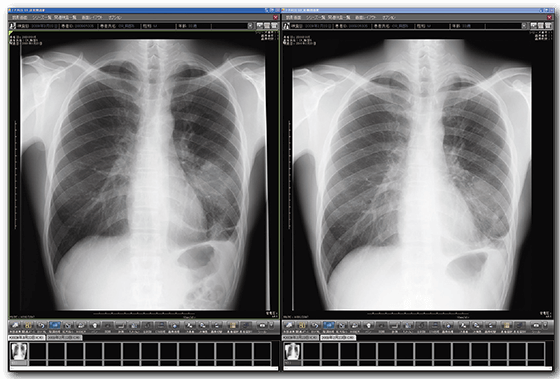

経時差分処理

経時差分処理は、種々の病態が存在する胸部単純X線画像の「現在」と「過去」の変化を比較して、差引いた画像を生成し「変化を可視化」することで、読影を支援する画像処理技術です。 経過観察時などにおける、視認性の向上や時間短縮が期待でき、多忙な先生方の読影業務を強力にサポートいたします。 ※オプション

診断支援

◆変化が可視化され、新規病変の認識がしやすくなる。

◆肺門部や心臓裏の見落としやすい部位の病変が見つけやすくなる。

◆過去画像と現在画像の比較により経時的変化が画像化され、経過観察が容易になる。